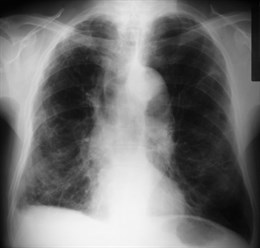

La exposición laboral a tóxicos inhalados causa más casos de enfermedad pulmonar obstructiva crónica (EPOC) en España que la exposición al humo de la biomasa, tal y como ha puesto de manifiesto el estudio ‘Exposición laboral y a biomasa en la enfermedad pulmonar obstructiva crónica: resultados de un análisis transversal del estudio On- Sint’, liderado por el neumólogo y miembro de la Sociedad Española de Neumología y Cirugía Torácica (SEPAR), José Luis López Campos.

La biomasa es la materia orgánica, que mediante la combustión, proporciona energía. Esta combustión produce humos que pueden ser inhalados, lo que en los sujetos sensibles provoca un cuadro de inflamación bronquial, con una obstrucción bronquial secundaria que en muchos aspectos es indistinguible de la EPOC.

En este sentido, la EPOC también puede estar causada por la exposición laboral al polvo, gases o productos químicos volátiles. Sin embargo, a menudo se observa que los pacientes expuestos a estas sustancias también fuman, por lo que en ocasiones es difícil determinar en qué grado ha contribuido cada sustancia al desarrollo de la EPOC.